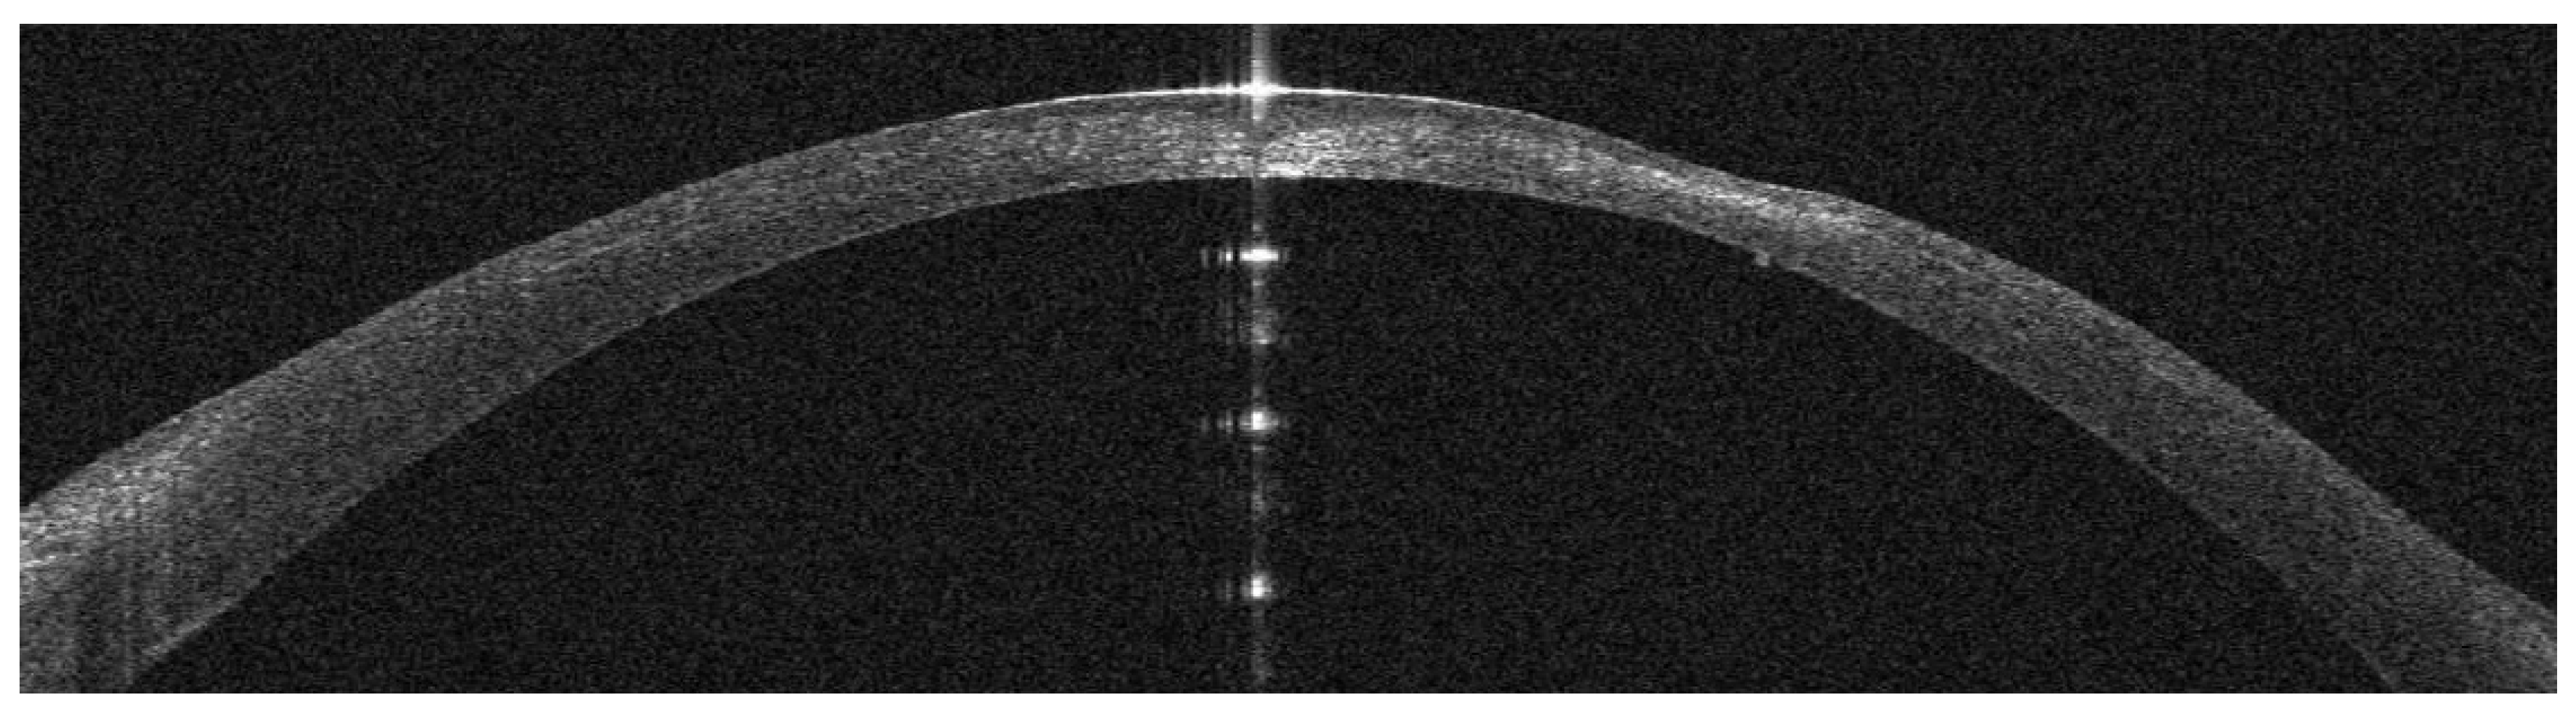

Infectious Keratitis Post-Femtosecond LASIK

AS-OCT Features